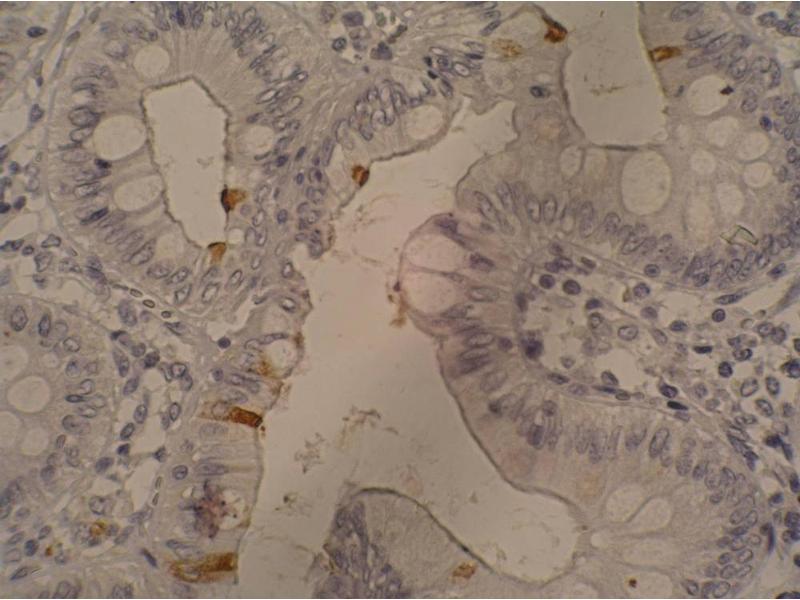

Il existe 1 publication pour ce produit. L’anticorps anti-CA 19-9 Monoclonal Souris est utilisé pour la détection de CA 19-9 dans des échantillons de Humain. Il a été validé pour ELISA et IHC (p).

ELISA, Immunohistochemistry (Paraffin-embedded Sections) (IHC (p))

The antibody 121SLE recognizes Sialyl Lewis a-containing glycolipids (extracellular plasma membrane leaflet antigens).

Immunohistochemistry (paraffin sections): Recommended dilution: 10 μg/mL, positive control: colorectal adenocarcinoma, heat mediated antigen retrieval (sodium citrate), mAb incubation 1 hour / RT, detection DAB.